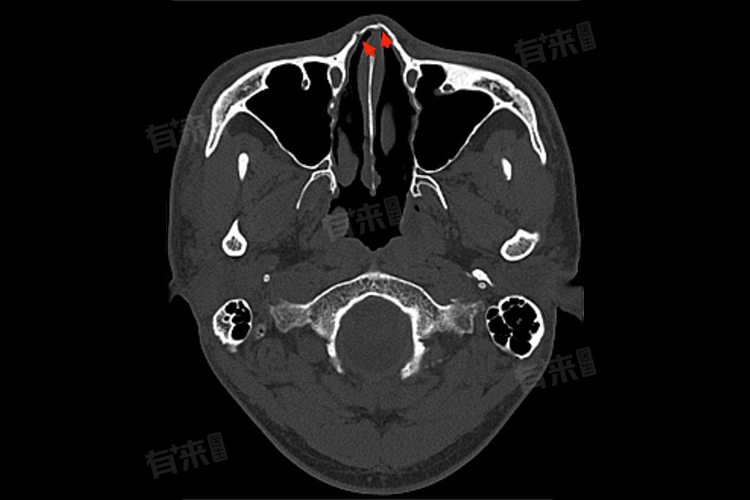

在恢复期间,应佩戴鼻子固定器或使用纱布来稳定鼻子,避免碰撞或剧烈运动导致鼻子再次受伤。在骨折初期,可以应用冷敷物来减轻鼻部肿胀和疼痛。当鼻腔内存在骨折时,用力擤鼻可能会导致骨头错位或再度骨折。发生鼻骨骨折后,应及时就医进行X光或CT检查,以明确骨折的程度和类型.